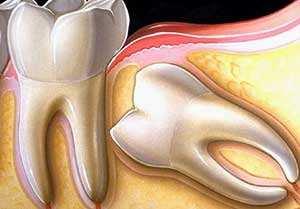

啥事阻生智齿呢?指的是跟相邻的牙齿产生抵触的智齿,相邻的牙齿抑制了你的智齿的生长,这样的智齿非常容易肿痛和发炎,甚至会顶坏你的好牙。

这类智齿由于生长空间不足,会使劲儿顶住相邻的牙齿继续生长,把邻牙顶歪、顶坏等等,与前牙牙缝处也容易出现龋洞,可能导致两颗牙齿都保不住。

首先你要祈祷自己长的不是阻生智齿,什么是阻生智齿呢,简单说就是口腔骨骼没给它留位置,它偏要钻出来,而且还是斜着长,甚至横着长,这种智齿及其霸道,当着其他牙齿的面和旁边牙齿秀恩爱,俗话说的好,秀恩爱死的快,阻生智齿十分容易把前面的牙齿顶坏,所以这种是必须拔掉的,严重的还会导致牙齿的变形,不整齐。